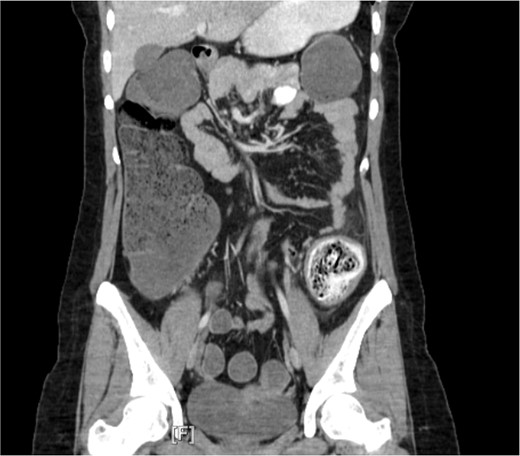

Repeat CT abdomen and pelvis (Fig. 1) found a mechanical large bowel obstruction secondary to distal impacted fecal matter in the descending colon along with segmental wall thickening with concern for fecaloma. Upon further questioning, the patient denied any ingestion of foreign objects or any previous history of irritable bowel syndrome. She mentioned adequate daily fluid intake and a moderate-fiber diet. She also mentioned never having any issues of constipation in the past, and denied any personal or family history of ulcerative colitis or Crohn’s disease. Due to the longevity of symptoms and CT scan findings, the patient was admitted with consultation to colorectal surgery and gastroenterology. Additionally, a bowel regimen with senna glycoside and docusate sodium was administered.

Computed tomography imaging revealed a mechanical bowel obstruction at the distal descending colon secondary to impacted fecal matter with noted colonic wall thickening and edema.